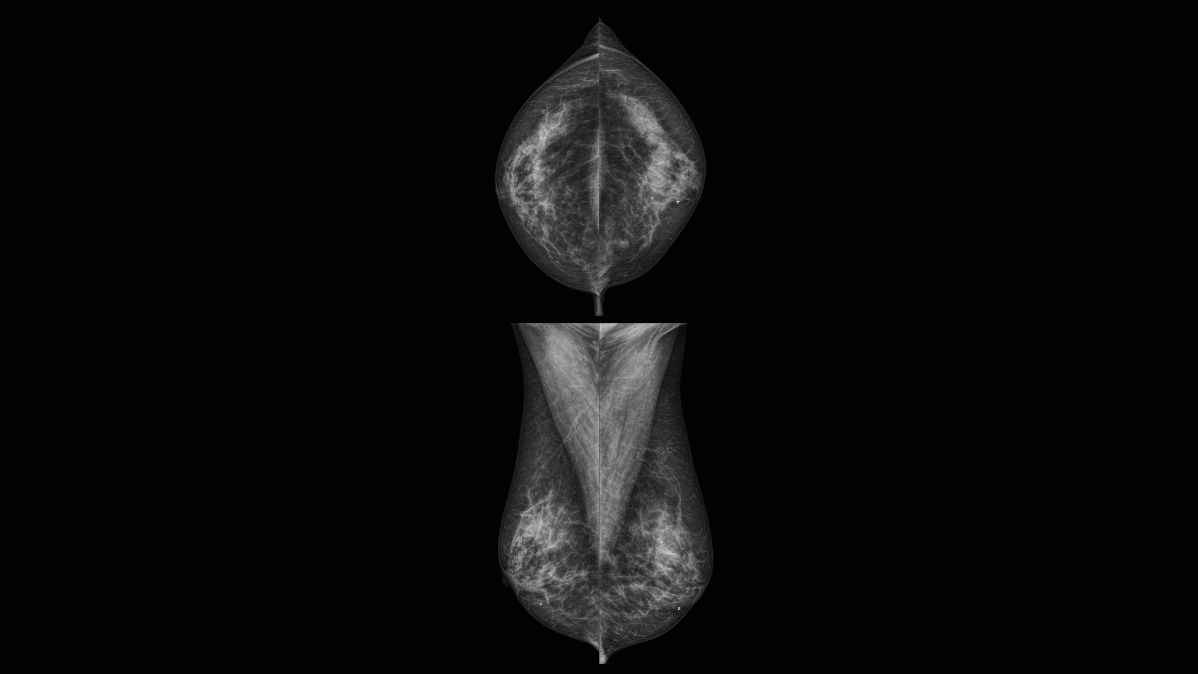

Obrazy Kliniczne Planmed Clarity 2D